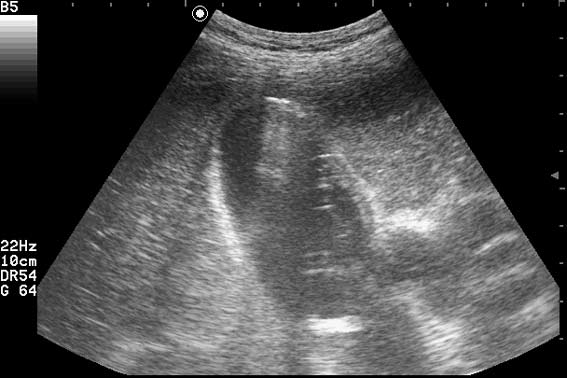

УЗИ Острый эмфизематозный холецистит. Эмпиема.

Пациент поступил в хирургическое отделение с жалобами на боли в правом подреберье и эпигастрии, повышение температуры. Болен 4 дня.

Острый эмфизематозный холецистит. Эмпиема ЖП. Паравезикул. абсцесс???